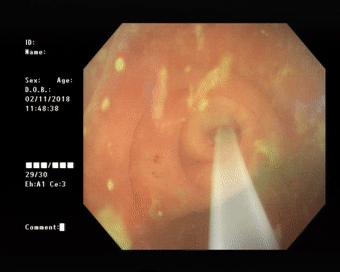

做好肠道准备后于31日上午在内镜室进行了内镜下逆行阑尾炎治疗术,镜下可见阑尾开口呈半月形,边缘粘膜充血、水肿,并有大量脓液流出,随在斑马导丝引导下将导管引导入阑尾腔用生理盐水进行阑尾腔反复冲洗并用替硝唑保留阑尾灌注,术后,患者自诉腹痛明显缓解。

镜下可见